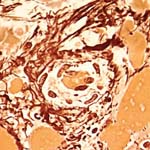

Knochenmarkschnitte können mit Hämatoxilin-Eosin und Giemsa gefärbt werden. Eine weitere verwendete Färbung ist die Chlorazetat-Esterase (siehe untenstehendes Bild), bei der sich die Zellen der Granulopoiese rot anfärben.